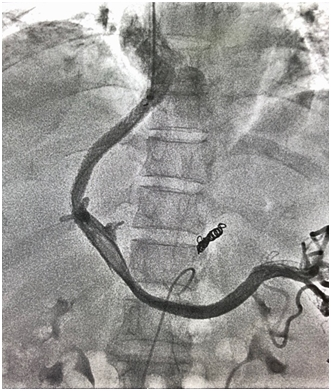

5月5日下午,在中山一院李家平主任及其技术团队的指导下,对患者进行右股动脉穿刺腹腔干造影及间接门静脉造影、右颈内静脉穿刺、经肝中静脉门静脉穿刺、门静脉置管造影、球囊扩张穿刺道及Viator专用支架置入、胃冠状静脉塔形钢圈栓塞等复杂而精细的操作,患者门静脉压力下降,门静脉体静脉分流成功。患者术后恢复良好,腹胀感缓解,腹水逐渐消退。

TIPSS为外周介入高难度手术,适应证有食管胃静脉曲张破裂出血、难治性腹水、难治性肝性胸腔积液、肝肾综合征、布加综合征、门静脉血栓等,本例TIPSS的成功开展,标志着我院在开展高难度介入手术领域再上新台阶。